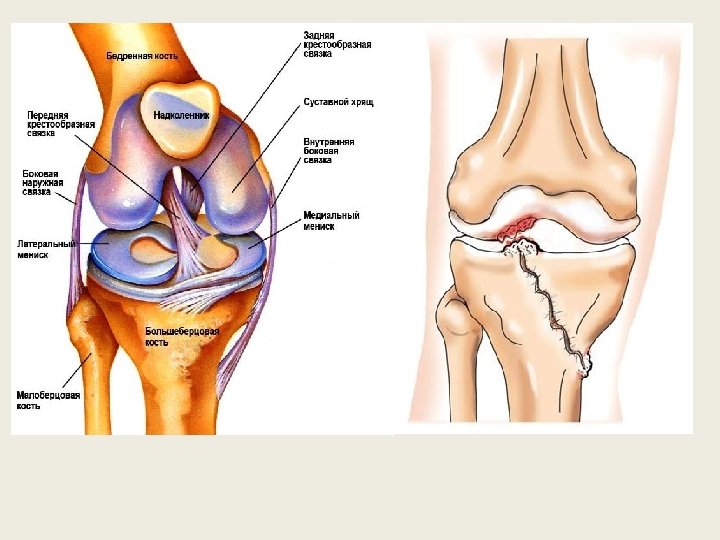

Поражения суставов, протекающие с болями и относящиеся к клинике внутренних болезней, можно подразделить на 4 большие группы. 1. Воспалительные ревматические поражения суставов. 2. Туберкулезные поражения суставов. 3. Дегенеративные поражения суставов. 4. Поражения суставов при различных общих заболеваниях. Всегда следует помнить, что боли в суставах могут быть обусловлены общими, хирургическими или травматическими заболеваниями.